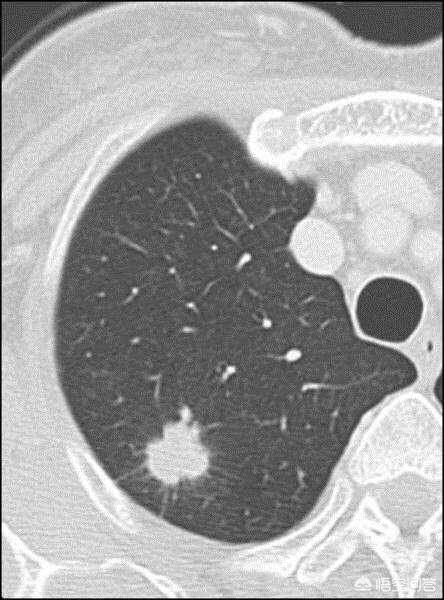

肺结节的CT影像中有一类特殊的影像-肺部磨玻璃结节,需要重点讲述。磨玻璃结节是一个影像学概念,指在高分辨CT上表现为密度轻度增加,呈云雾状密度阴影,其内支气管及血管纹理仍可显示。磨玻璃结节恶性概率高于实性结节。2018年NCCN肺癌筛查指南建议:小于6mm的的纯磨玻璃结节,无需常规随访;结节在6mm以上的纯磨玻璃结节,建议6-12个月确定稳定性,之后每2年复查直至5年。部分实性磨玻璃结节中如果实性成分大于6mm的磨玻璃结节,建议3-6个月确定稳定性,实性成分大于6mm且高度怀疑肺癌时才建议行活检或者手术切除。